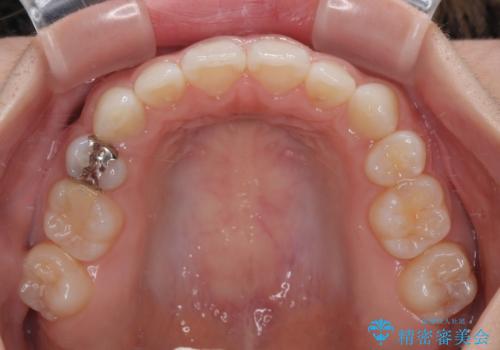

矯正治療後には、目立っていた奥歯の銀歯をオールセラミッククラウンへ作り替え、スッキリした口元に仕上がりました。